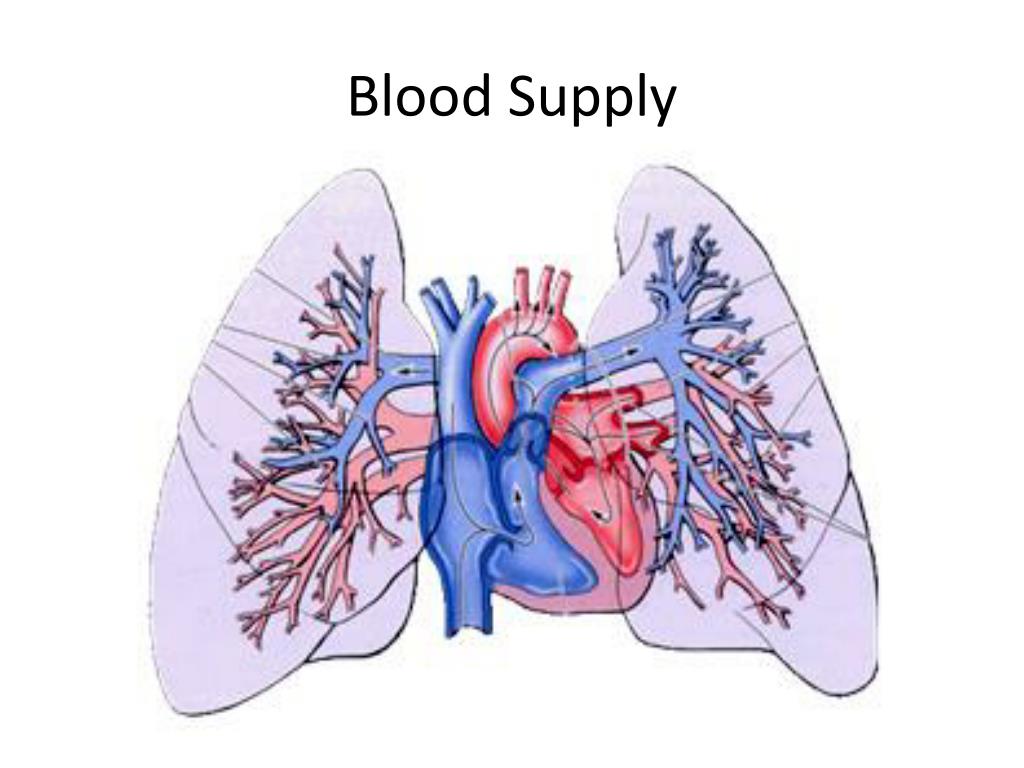

Особенности и диагностика левостороннего кровотока